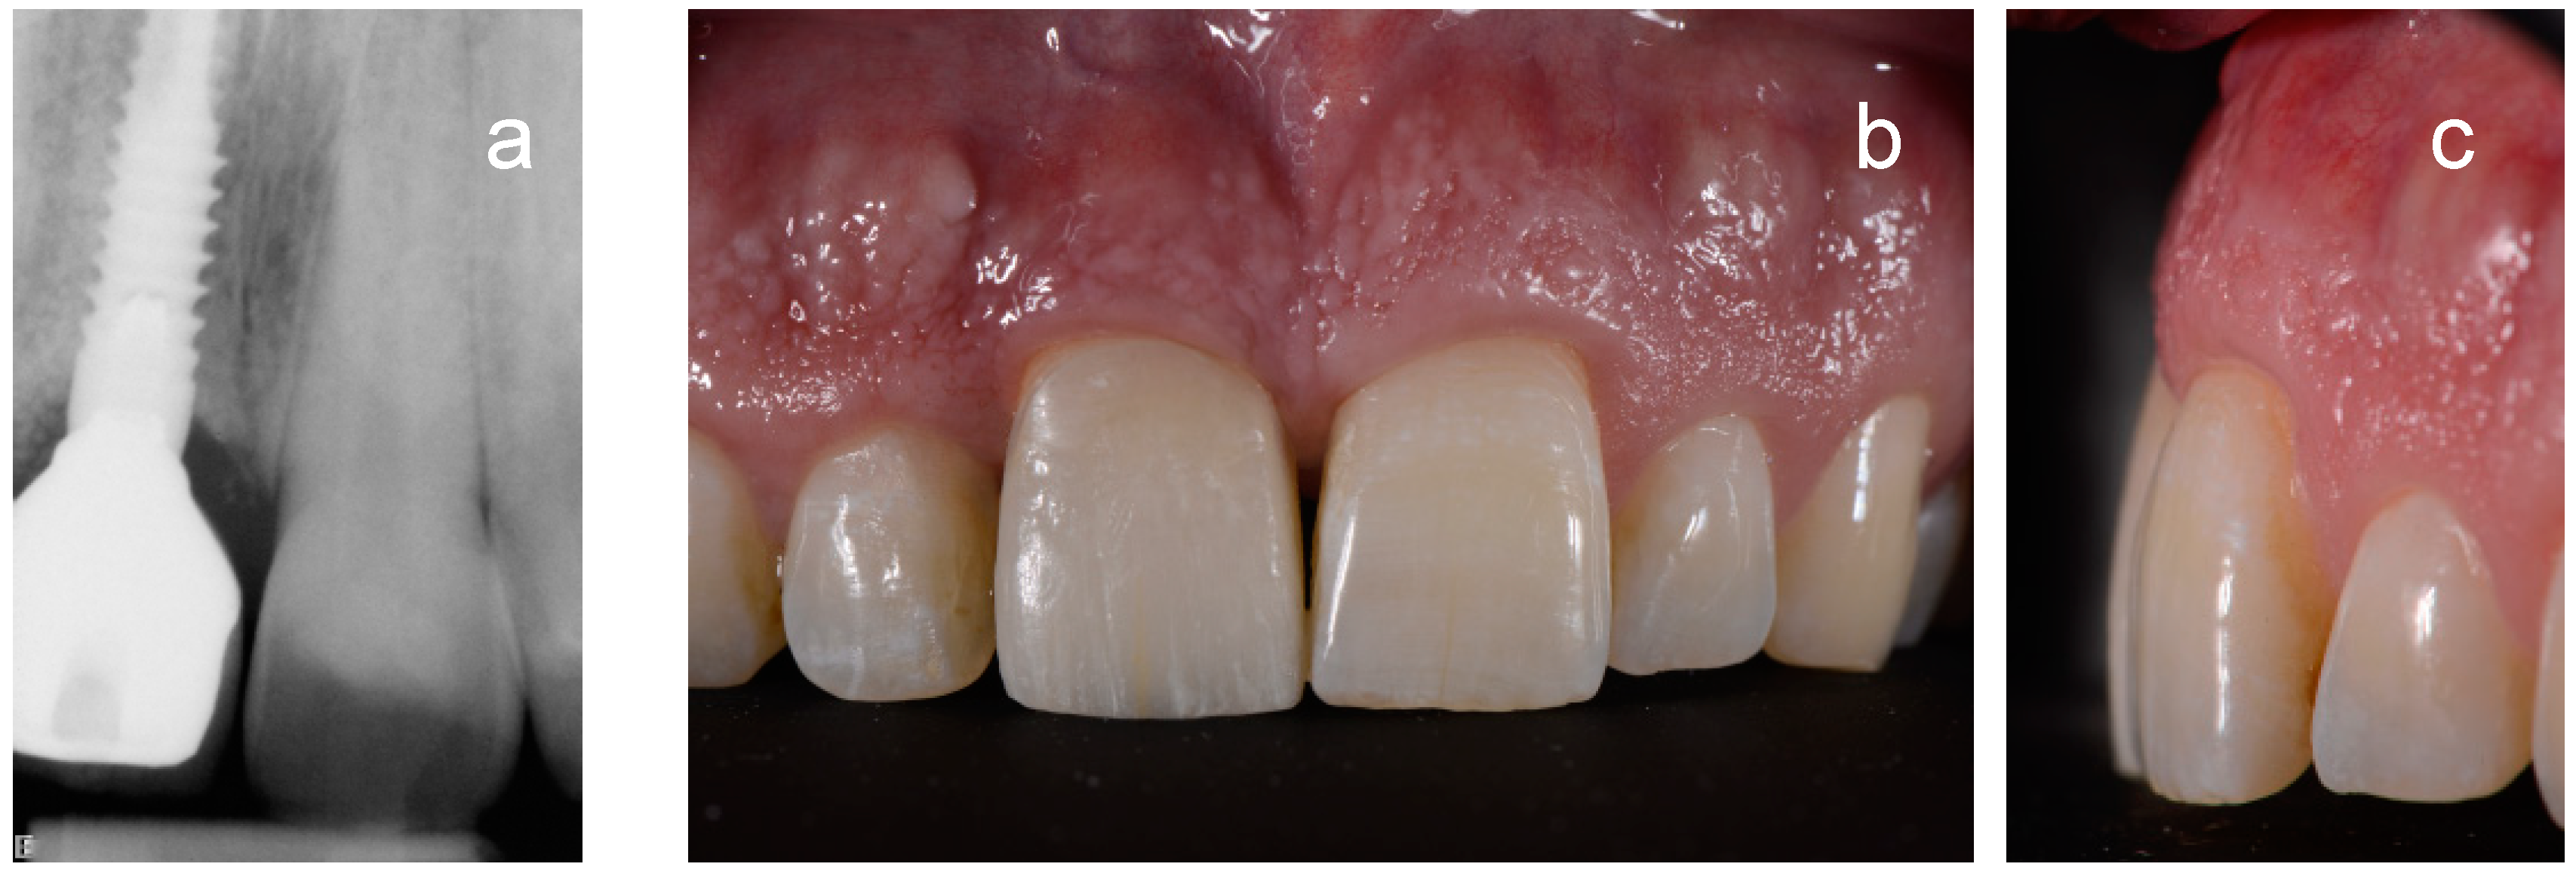

3. Results